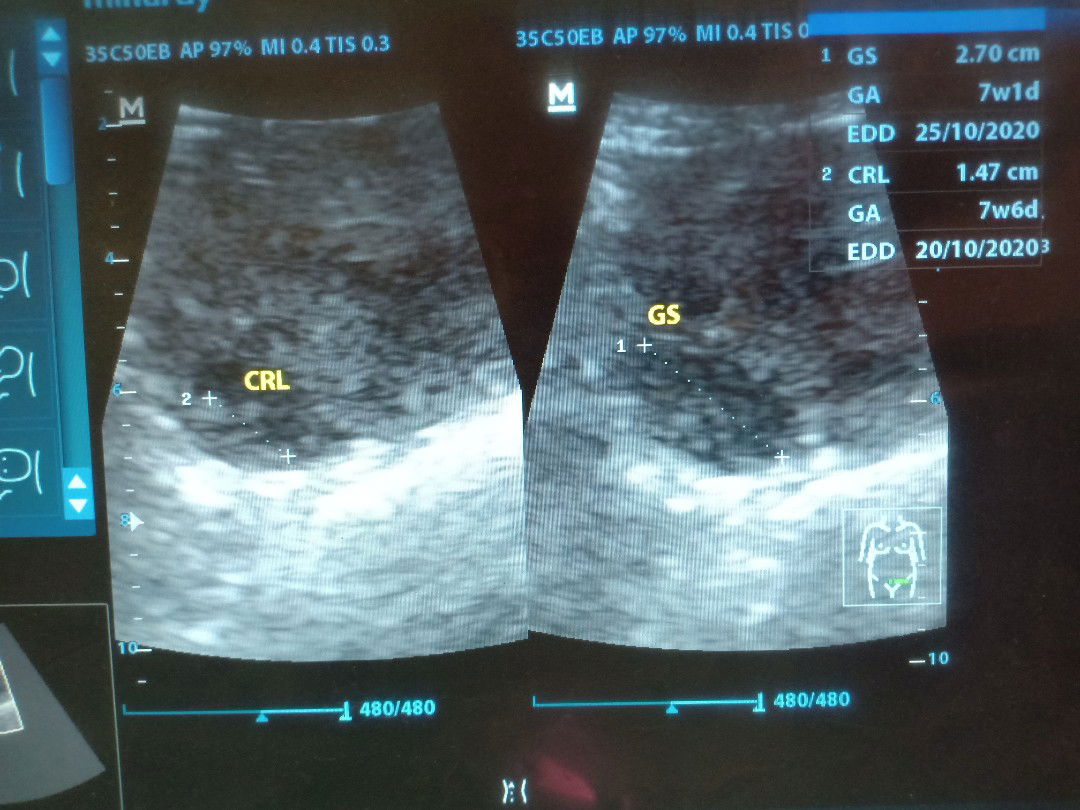

USG

Bun maaf ya mau tanya ini saya usg di awal kehamilan, dokternya bilang di gambar pertama itu ada janinnya kecil, dan gambar kedua itu kantongnya. Tapi kok aku masih ragu ya bun, apa aku kurang teliti liatnya ? Kira2 menurut bunda2 itu keliatan gak sih ada janinnya (putih2) ? Sama dokternya di suruh balik 2 minggu lagi, tapi sama ibu disuruh nunggu kalo sudah 4bulan. Aku jadi takut sendiri liatnya bun ??